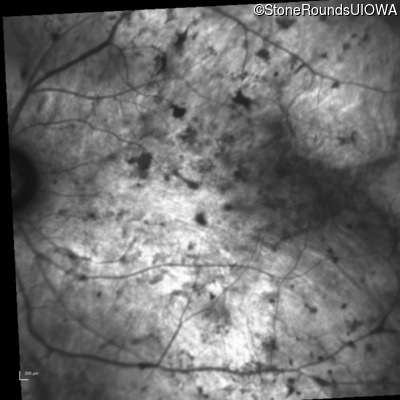

Age at visit: 61 years